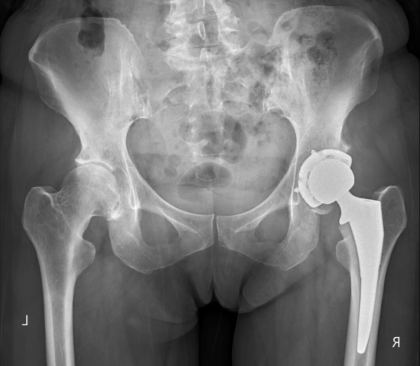

人工股関節置換術とは

人工股関節置換術(Total Hip Arthroplasty - THA)は、病気や怪我によって損傷し、機能が低下した股関節を、人工的に作られた関節(インプラント)に置き換える手術です。この手術の主な目的は、股関節の痛みを大幅に和らげ、関節の動きや安定性といった機能を回復させることで、患者様の生活の質(QOL)を総合的に向上させることにあります。

手術では、股関節の損傷した部分、具体的には大腿骨の先端部分である「ボール」の役割を果たす大腿骨頭(だいたいこっとう)と、骨盤側で「ソケット」の役割を果たす寛骨臼(かんこつきゅう)を取り除き、金属、ポリエチレン、セラミックなどでできた人工部品に置き換えます。